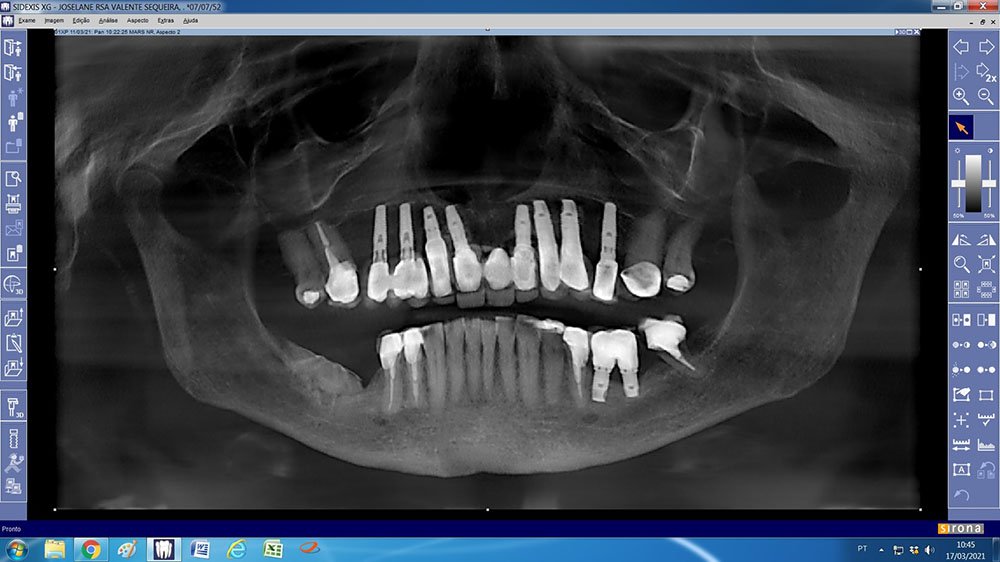

Neste relato, apresentamos um caso clínico onde necessitamos realizar um aumento ósseo vertical e horizontal, no qual optamos por utilizar um biomaterial composto de colágeno tipo 1 e hidroxiapatita bovina (Extra Graft), e uma membrana de PTFE denso com reforço de Titânio (Cytoplast TI-250) para realizar a regeneração óssea guiada na região posterior da mandíbula.